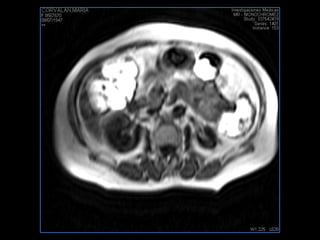

PROTOCOLO abdomen COR T2, AXIAL supresion grasa AX T1 +SAG T2  CON   GADOLINIO :  COR T1+AX T1(DIN) SAT: NO  FASE: RL THK: 6MM  COIL:  GAP: (FACTOR 1.4) 2MM FOV: 40 CM NEX:2 SINCRONIZACION RESPIRATORIA EN 3 O 4 CICLOS ALE

PROTOCOLO pancreas/ riñon AXIAL fat sat /AX in phase out phase AX T1 +SAG T2  COR T2, CON   GADOLINIO :  COR T1+AX T1(DIN) SAT: NO  FASE: RL THK: 4MM  COIL:  GAP: (FACTOR 1.4) 1MM FOV: 40 CM NEX:2 SINCRONIZACION RESPIRATORIA EN 3 O 4 CICLOS ALE

resonancia de abdomen